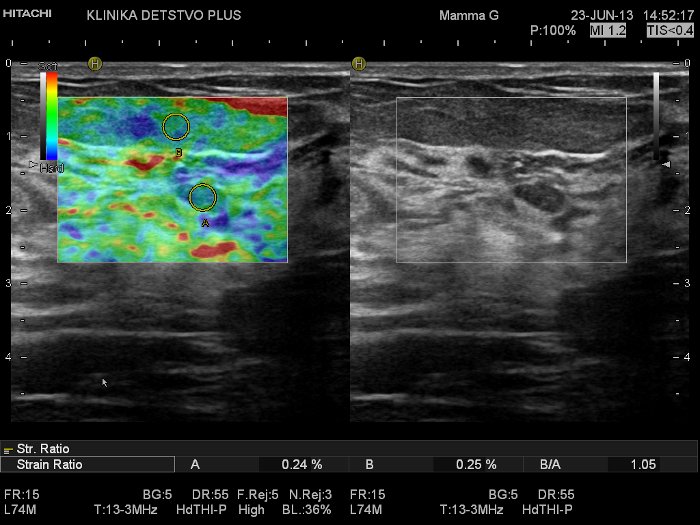

Впрочем, самое главное для пациентов, конечно, заключается в том, что вместе с аппаратом Hitachi Hi Vision Preirus в зеленоградскую медицину пришла соноэластография — новейший метод выявления опухолей на самых ранних этапах развития. — Любая ткань организма обладает определенными свойствами, в том числе — плотностью, эластичностью. Различные заболевания эти свойства ткани меняют, — объясняет Елена Алексеевна. — Так, воспалительные процессы и опухоли приводят к размягчению или уплотнению ткани, вследствие чего меняется ее эластичность. Соноэластография позволяет сравнивать эхосигнал, получаемый от патологического участка и здоровых тканей при нагрузке — мягком давлении обычным ультразвуковым датчиком, и судить о доброкачественности или злокачественности процесса. Эта технология применяется при исследовании молочных желез, щитовидной железы, лимфоузлов, мышц, других поверхностно расположенных органов и образований, органов малого таза у мужчин и женщин, некоторых внутренних органов.

Соноэластография дает врачу возможность четче визуализировать подозрительные образования в тканях, которые плохо различаются при исследованиях на обычных УЗ-аппаратах, и более точно определить истинные размеры опухоли. Этот метод позволяет дифференцировать кисту или воспалительный процесс, но, наверное, самое важное достижение соноэластографии заключается в возможности провести границу между доброкачественными и злокачественными опухолями.

— Смотрите — вот здесь, справа, у нас есть образование, похожее на злокачественное — Елена Алексеевна демонстрирует сонограмму с изображением небольшого участка, который внешне отличается от окружающей ткани. — Простым переключением аппарата мы выходим из обычного УЗ режима и попадаем в режим соноэластографии. Причем результаты видим в реальном времени. Все участки тканей в зависимости от их эластичности окрашиваются своим цветом. Наименее эластичные, плотные — синими оттенками, среднеэластичные и мягкие – оттенками зеленого и красного цветов соответственно. Наш подозрительный участок окрасился преимущественно в оттенки зеленого цвета, то есть он достаточно эластичный, и мы можем предположить доброкачественный характер изменений ткани. Поэтому пациент не будет подвергаться пункции для взятия материала на цитологию или гистологию, тратить на это свое время и испытывать дополнительный стресс. В данной ситуации показано динамическое наблюдение, а раньше пришлось бы делать биопсию.

Изображение тканей в режиме соноэластографии на приборе Hi Vision Preirus (Hitachi): доброкачественный характер очаговых изменений

Изображение тканей в режиме соноэластографии на приборе Hi Vision Preirus (Hitachi): доброкачественный характер очаговых изменений